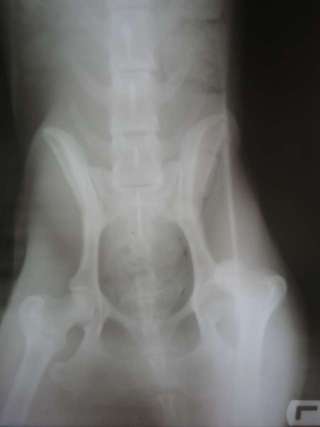

| Rasse: | Galga | Geboren: | 2008 |

Man muss Angelie lediglich beim Rennen noch ein wenig bremsen, damit sie es mit ihrem Beinchen nicht übertreibt. Mit unseren 5 Katzen und den 4 Schopfhunden kommt sie mittlerweile auch gut aus. Sie möchte aber immer "Chefin" von allen sein (auch von mir)!